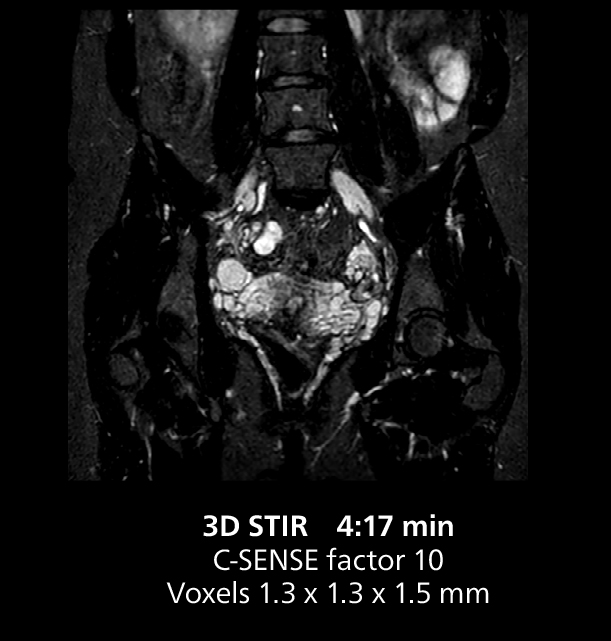

This MRI case illustrates good resolution and imaging quality obtained within reasonable scan times using the MR 5300 1.5T system with the anterior torso cardiac coil that allows use of a large field of view (FOV).